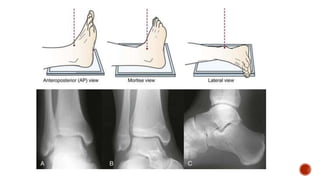

 Radiographic views for ankle joint

 INDICATION

 Ankle farcture/dislocation

 Talus involvement

 Osteoarthritis ankle

•The leg must be rotated internally 15° to 20°, thus aligning the

intermalleolar line parallel to the detector. This usually results in the

5th toe being directly in line with the center of the calcaneum

•To differentiate from AP – the tibia , fibula , talus overlap is gone